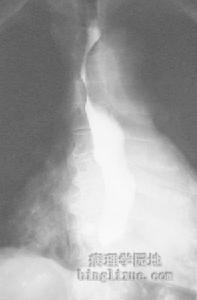

1.结肠镜检假膜性肠炎同时侵犯结肠,尤其是乙状结肠可借助结肠镜进行检查。有报道应用纤维结肠镜检查了16例假膜性肠炎的患者,其中有14例在直肠和乙状结肠部位发现了病变。典型的表现为黏膜发红水肿,上面有斑块或融合的假膜,活检可见黏膜有急性炎症,假膜内含有坏死上皮、纤维蛋白、炎性细菌等。应用纤维结肠镜检查时要掌握病程进展的阶段,肠炎尚未形成假膜或局部的假膜已经脱落时镜下未必能发现假膜,所以不一定以假膜为唯一的诊断根据,未见假膜并不一定能排除本病。假膜性肠炎病变可以呈跳跃式分布,为了防止遗漏小的病变,要求镜检的范围必须包括全结肠,在有代表性部位采取病变组织,采取活检时要有一定的深度。

2.腹部X线平片常有肠黏膜增厚、小肠胀气,部分肠麻痹病人表现为肠梗阻。钡灌肠可能发现肠管边呈毛刷状、指压迹症和散在的圆形、不规则形充盈缺损。气钡双重造影可提供更多的诊断指标,但必须小心操作防止肠穿孔的发生。